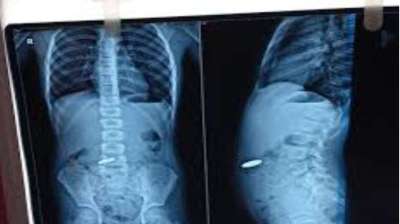

खिलौना नहीं सिक्का था! बच्चे ने निगले 5-10 रुपये के सिक्के, डॉक्टरों ने ऑपरेशन कर निकाले

दिल्ली : दिल्ली के एक सरकारी अस्पताल के डॉक्टरों ने 12 वर्षीय बच्चे की जान बचाई है। बच्चे ने पांच और दस रुपये के तीन सिक्के निगल लिए थे। सिक्के...